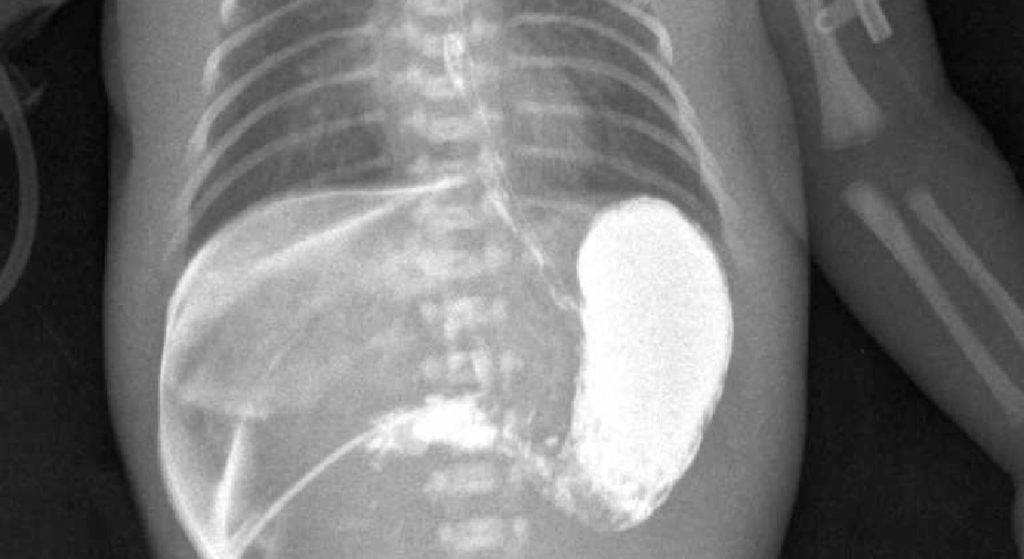

Также дополнительным методом исследования является рентгеконтрастирование – пассаж бария по ЖКТ. Хотя рентгенологическое исследование несёт лучевую нагрузку, оно является информативным и позволяет точно определить проходимость привратника. Ребёнку через рот даётся около 30 мл контрастного вещества (5% взвеси бария в грудном молоке или 5% растворе глюкозы). Обзорная рентгенография брюшной полости выполняется через час и четыре часа, после дачи контраста. При пилоростенозе на снимке будет определяться большой газовый пузырь желудка с одним уровнем жидкости. Эвакуация контраста из желудка в двенадцатиперстную кишку замедлена. После проведения обследования желудок необходимо опорожнить, чтобы при последующей рвоте предотвратить аспирацию бария.

Диагностика основана на проведении рентгенологического исследования с введением контрастного вещества в желудок.

- Рентгенограмма с контрастом – позволяет оценить проходимость желудка и указать на конкретный участок нарушения.